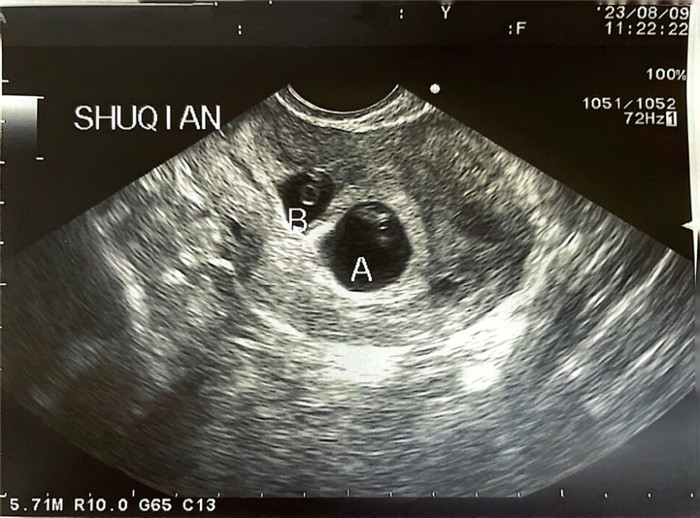

幸运的是,经过细致的超声评估梁女士子宫瘢痕处的肌层较厚、孕囊仅部分着床于此处,属于子宫瘢痕妊娠Ⅰ型,且宫内胎儿发育良好。在与梁女士夫妇充分沟通手术相关风险和并发症后,夫妻要求保留宫内胎儿意愿极为强烈。生殖中心医护团队为梁女士制定详细的手术方案,在做好备血、抢救准备后,于 8月9日在梁女士孕7周时,由经验丰富的刘风华主任医师为其进行阴道超声引导下胚胎减灭术,成功减灭子宫瘢痕处妊娠。术后住院安胎、观察,梁女士无腹痛、阴道流血的情况。术后一周复查超声,宫内胎儿发育良好。

手术前超声可见宫腔内正常妊娠的孕囊A和子宫瘢痕处妊娠孕囊B